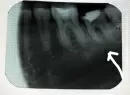

Дело в том, что по рентгенограмме определяется расширение периодонтальной щели и разрежение костной ткани в области бифуркации.

Решать Вам совместно с лечащим врачом о дальнейших мероприятиях. Возможны два варианта. Удаление и протезирование в дальнейшем. Либо попытаться сохранить зуб и наблюдать за ним в динамике. Но для этого все равно требуется установка коронки, так как разрушена большая часть анатомической формы зуба. Если зуб оставить с пломбой, то он в любой момент может расколоться от нагрузки.